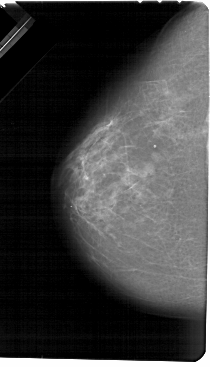

A_1328_1.LEFT_MLO

LEFT_CC LINES 5491 PIXELS_PER_LINE 3136 BITS_PER_PIXEL 12 RESOLUTION 43.5 NON_OVERLAY